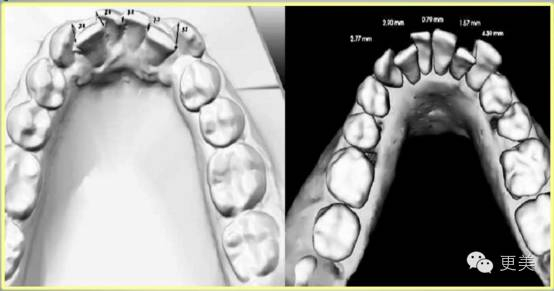

第三步:取膜,传统方法是用石膏材料制作患者的牙齿口腔模型,较为先进的方法是口内扫描,制作电子的三维立体模型。